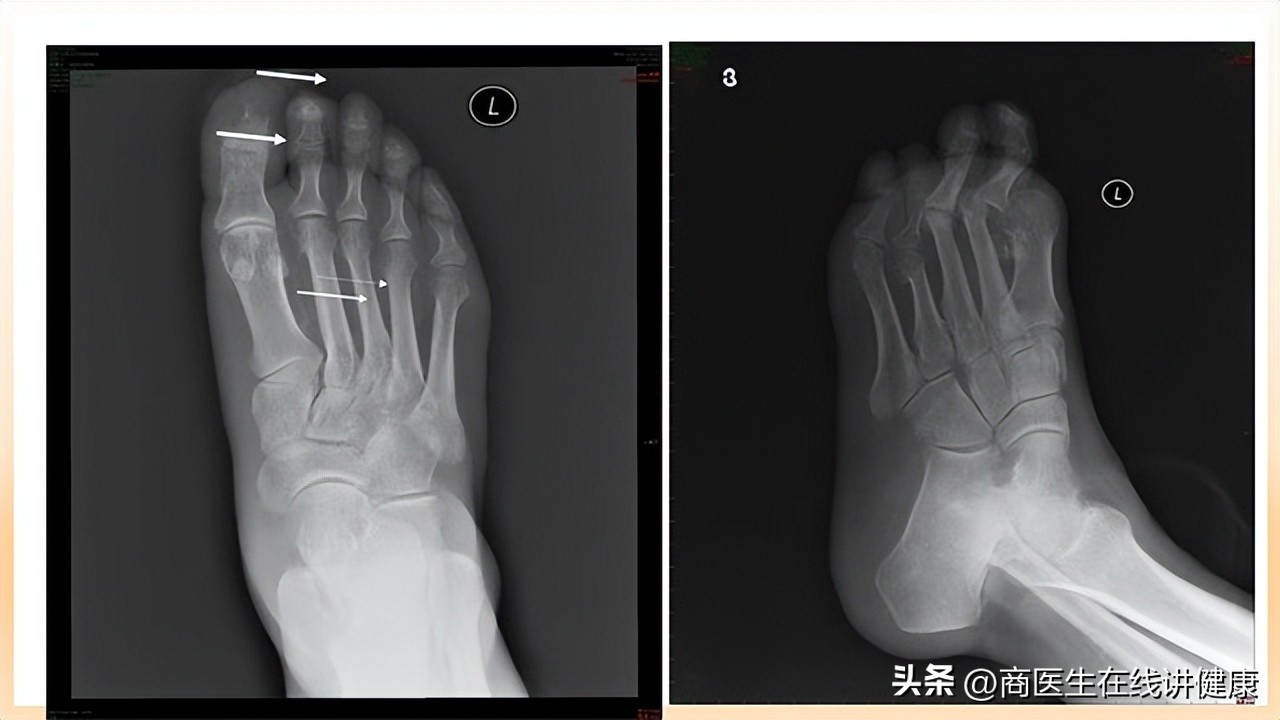

到我院后,医生询问张先生的 过往病史和主要病情 情况,以及做好基本体格检查后,怀疑张先生可能存在糖尿病足的情况,于是与张先生以及家属商量后,给予 血糖检测和足部X线平片检测,血糖检测结果显示10mmol/L,足部X线平片检测结果显示足部有周围末梢的骨质疏松,以及骨质水肿等不良营养情况的出现 ,检测结果均提示张先生患上了糖尿病足。